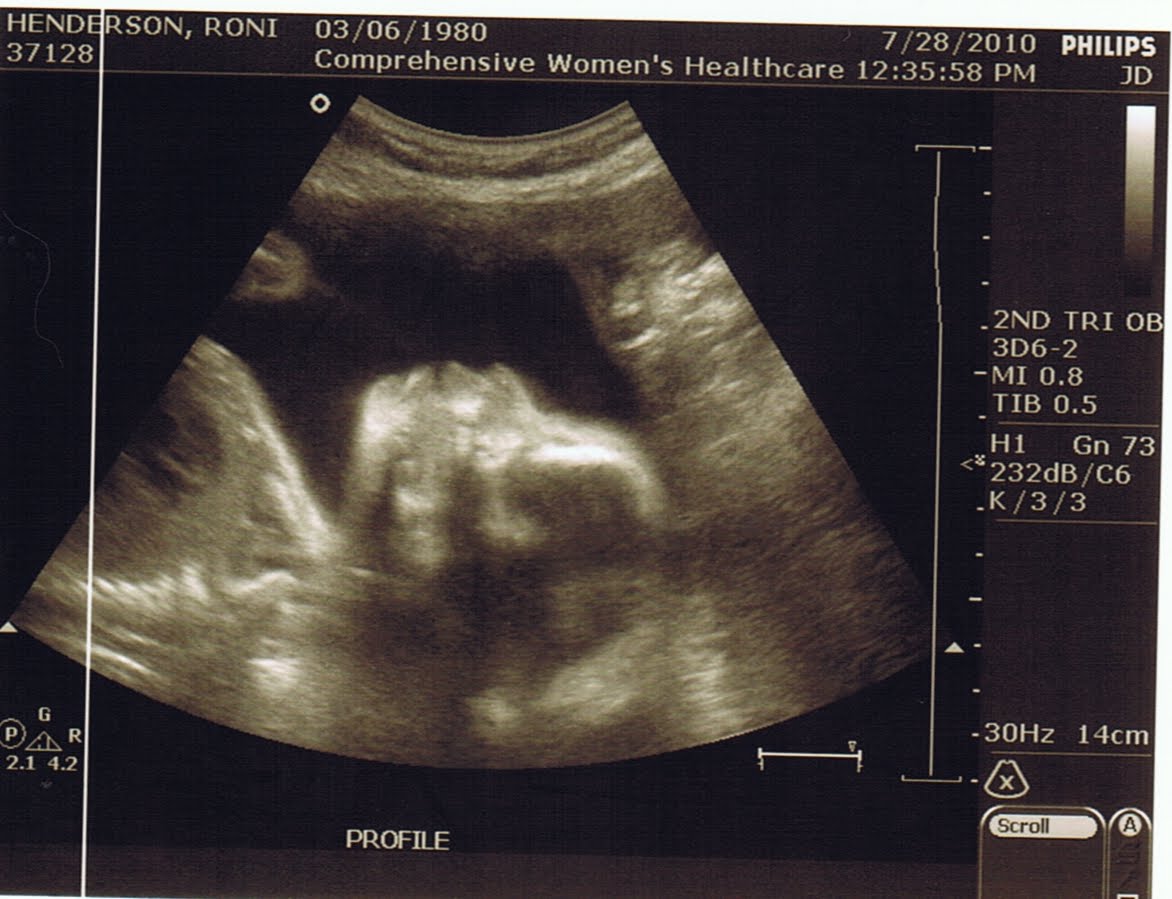

I had an ultrasound today to check for bone development. According to my doctor is the last thing that we can check for in a ultrasound to make sure there aren't markers for downs. And her long bones measured perfectly, actually a little ahead so even better. I think we are in the clear for downs. I am so glad.

The little girl looked perfect. She is measuring a week ahead and is already 1 lb 12 oz. The average for 25 weeks is 1 lb 6 oz. Hopefully she won't be too big of a baby or maybe I will get lucky and deliver a little early.

We got alot of really cute 3-D pictures this time and most importantly she is still a girl. I can't help but make them check every time I get to see her.